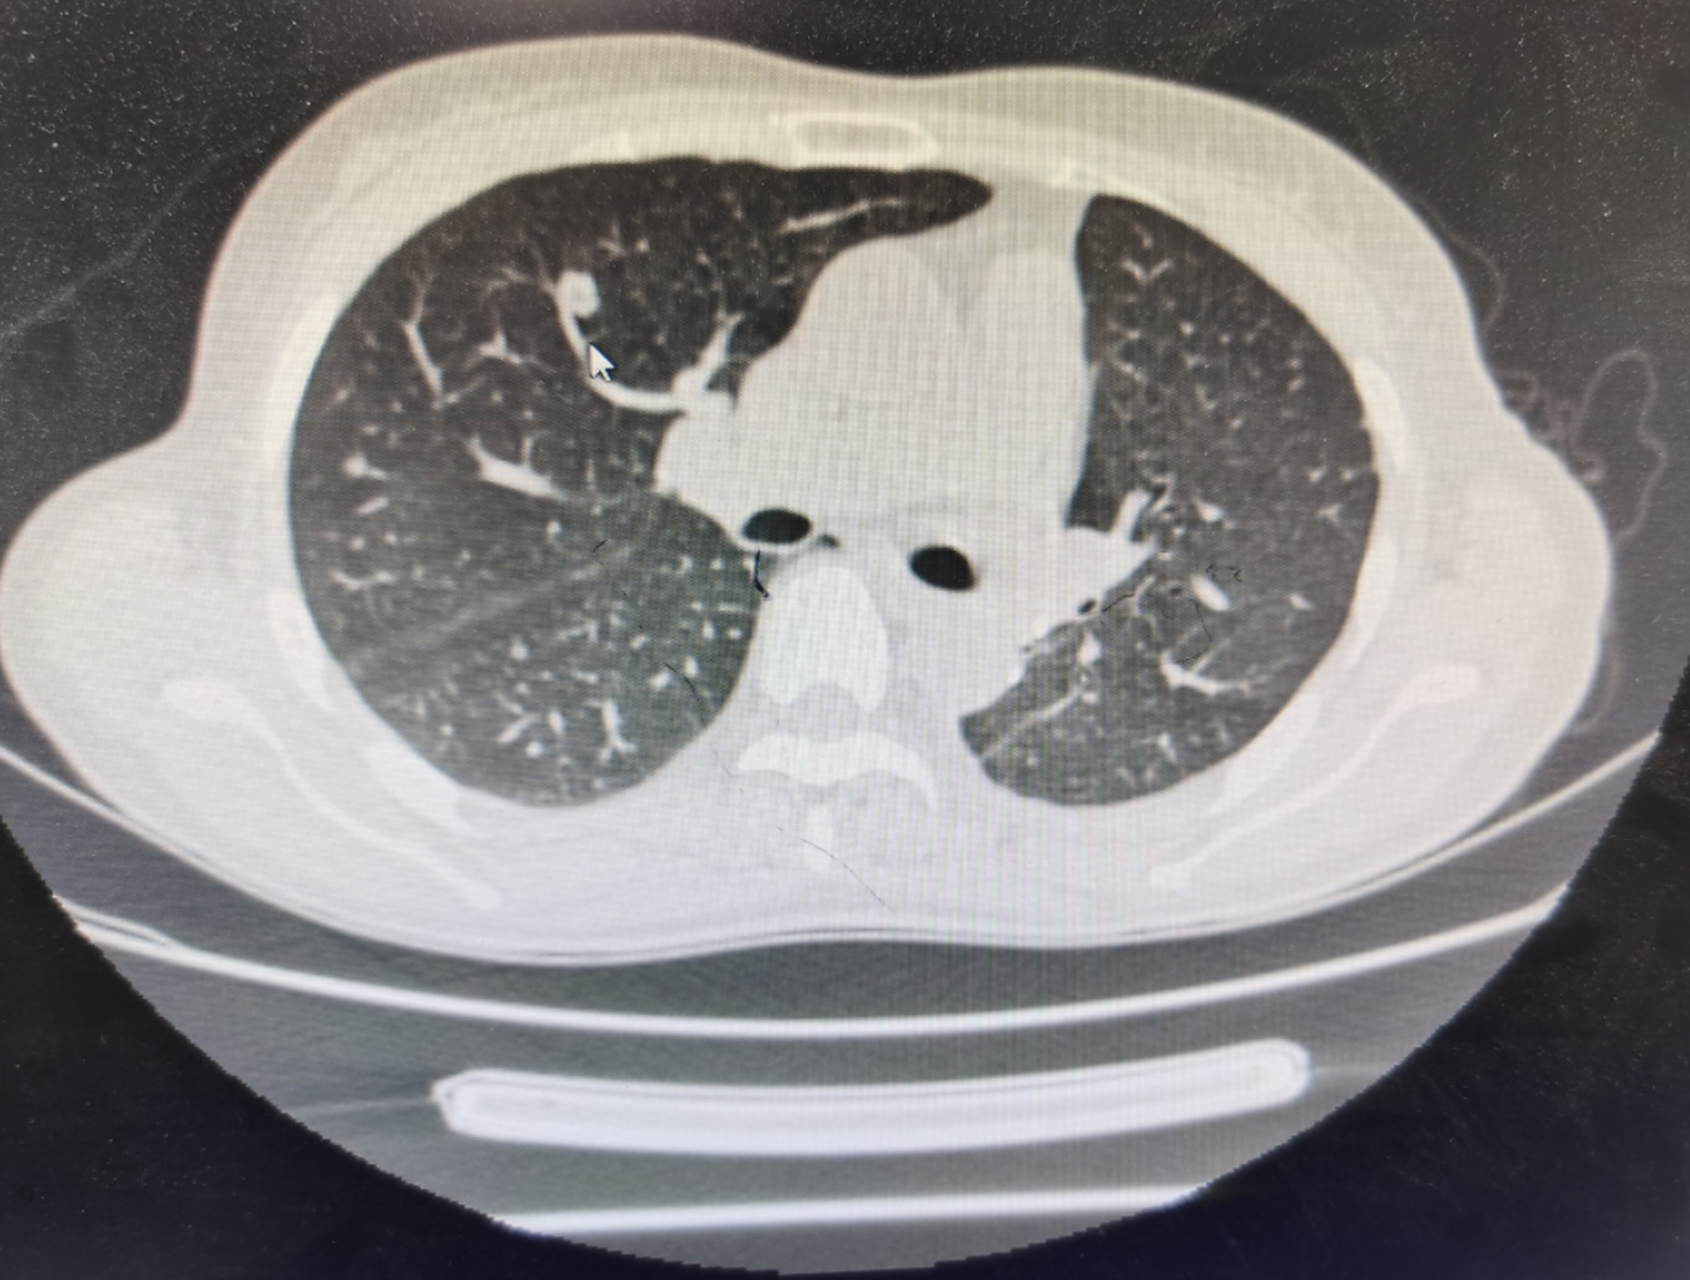

双肺纤维化病灶,说明病史很长.斑片状影,说明是活动性病灶.